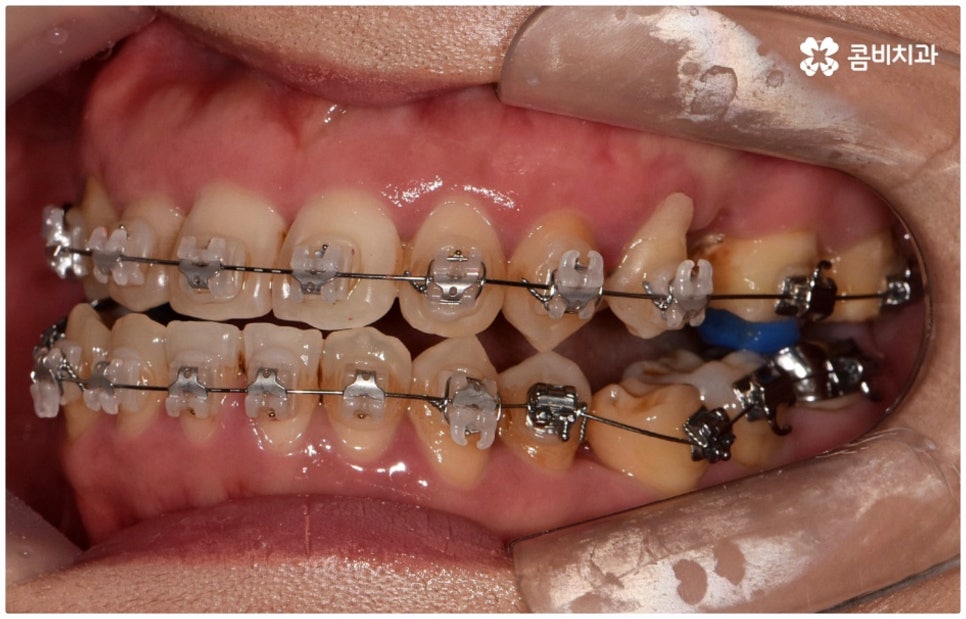

골격적인 원인으로 인한 것이라면 반대교합교정 치료를 할 때 위턱의 성장을 유도하고 상대적으로 아래턱 성장을 저지하는 방향으로 상악과 하악의 위치 관계를 개선하는 방법을 사용하게 되며 환자분들의 상황에 따라 악궁확장장치 또는 페이스마스크 등의 장치를 이용하게 되는데, 이렇게 골격적인 부분에 크게 영향을 받은 경우 재발의 가능성 역시 높기 때문에 어릴 때 교정 치료를 시작하여 치열이 고르게 돌아왔다고 해도 성장이 완료되는 시기까지 꾸준하게 관리를 해 줄 필요가 있어요.

교정 치료가 생물학적 반응을 이용하는 것이다 보니 성장기에 진행하면 치아 이동 및 회복 속도 등에 장점이 있는 것은 분명하지만 그렇다고 해서 성인 이후 중장년 분들이 교정 치료를 받을 수 없는 것은 아니며 이미 많은 분들이 도움을 받고 계신 만큼 이에 대해서 한 번 고려해 보시면 좋을 거예요. 혹시 성장기 이후로는 양악 수술 등으로만 치료가 가능한 것이 아닐까 생각하셔서 부담스럽게 느끼셨던 분들이라면 지레 겁을 먹고 불편함을 그대로 방치하시기 보다는 검진 및 상담을 통해 적극적으로 이를 해결해 보시길 권유드리고 있어요.

물론 원인과 정도에 따라 외과적인 방법이 필요하신 분들도 있을 수 있지만 교정을 통해 얼마든지 치료가 가능한 경우도 있으며 앞서 말씀드렸던 것처럼 발전된 교정 기술 및 특수 미니스크류 등의 장치 개발을 통해 턱의 방향을 조금씩 회전시켜 원거리 치아 이동을 유발하는 것이 가능해졌기 때문에 예전에는 한계가 있었던 부정교합 케이스도 개선될 여지가 늘어나고 있습니다. 꼼꼼하게 검진을 받으시고 자신의 상황에 맞는 교정 치료를 무리하지 않게 진행하신 후 철저하게 사후 관리를 해주시면 보다 오랜 기간 동안 건강하게 고른 치열을 유지하면서 생활하실 수 있을 거예요.